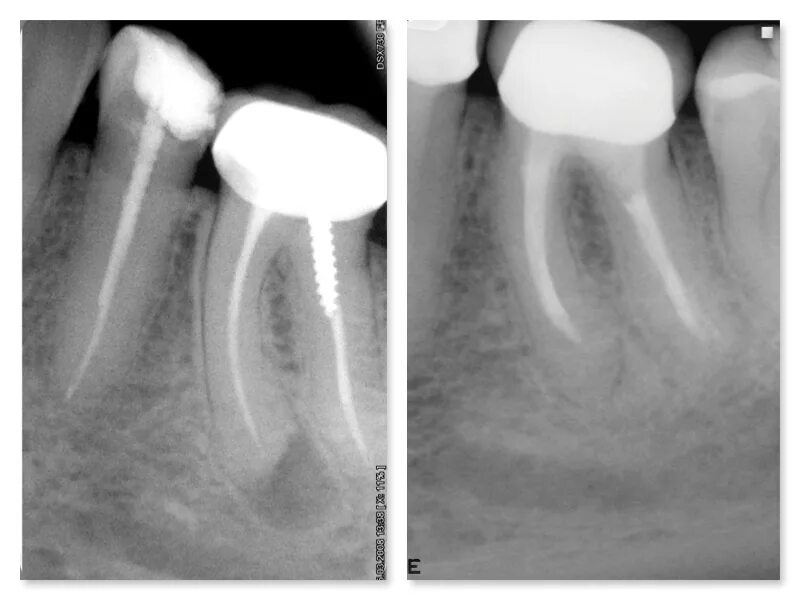

Киста зуба что это